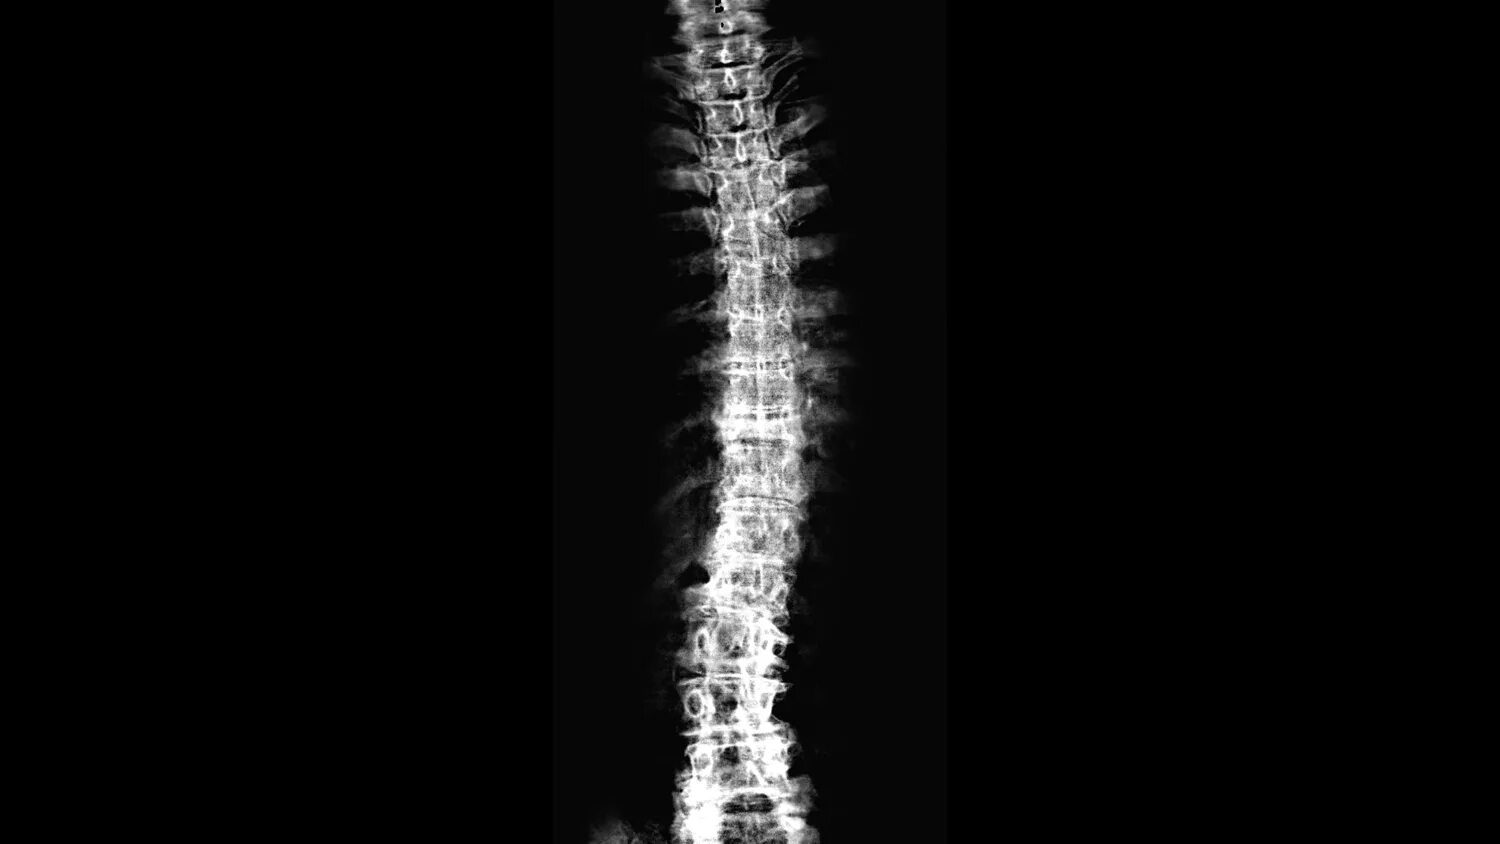

Backbone s